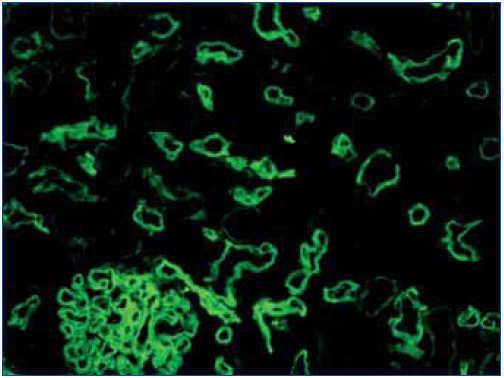

Existen dos métodos de detección de C4d: inmunofluorescencia indirecta (figura 2) e inmunohistoquímica (figura 3).

1. La inmunofluorescencia indirecta (en dos o tres pasos), con anticuerpo monoclonal anti-C4d, es un método sensible, reproducible y sencillo de interpretar. Sin embargo, presenta una serie de inconvenientes: no funciona en material fijado en formol e incluido en parafina, por lo que es necesario disponer de material congelado y, además, no es permanente y se deteriora con el paso del tiempo. En nuestra experiencia, la inmunofluorescencia es el método gold standard para la detección de C4d.

Figura 2. Depósitos de C4d. Inmunofluorecencia.